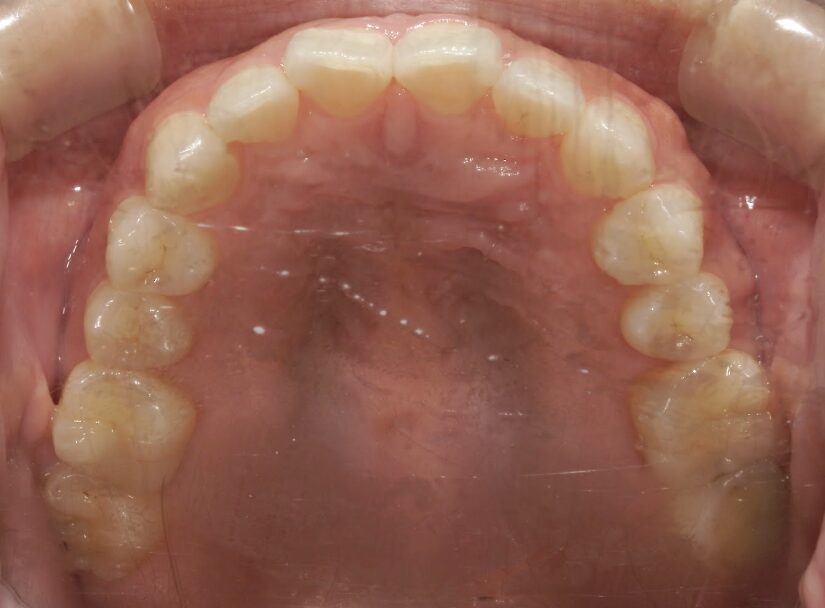

過蓋咬合

治療前

ガタガタを主訴に当院を受診され、上下前歯部に叢生(ガタガタ)と過蓋咬合(上の歯が下の歯を深く覆いかぶさっている状態)を認めました。